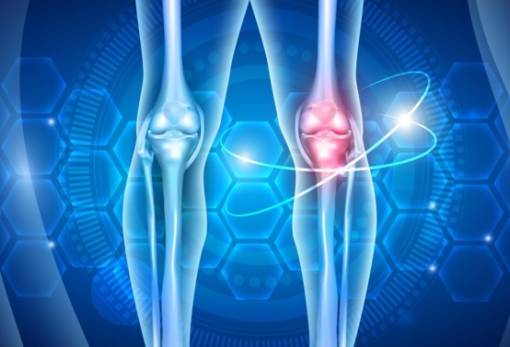

Dr Αντώνης Θεοδωρίδης: Εξειδικευμένη αντιμετώπιση στις μυοσκελετικές παθήσεις και ορθοπαιδικές κακώσεις

Ο Dr Αντώνης Θεοδωρίδης μιλά για όλα όσα πρέπει να γνωρίζουμε

Ρήξη Πρόσθιου Χιαστού Συνδέσμου: Ο Dr. Αντώνης Θεοδωρίδης μιλά για όλα όσα πρέπει να ξέρετε

Πως βοηθάει η εξωαρθρική τενόδεση